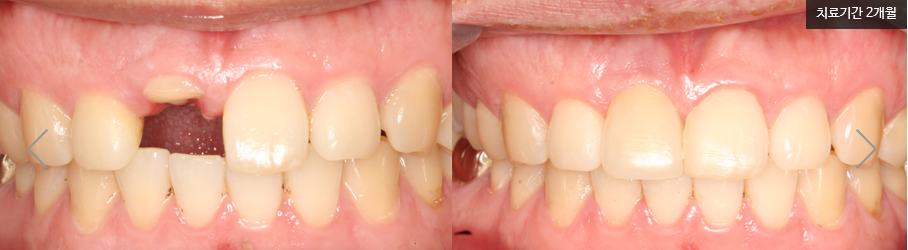

실제 명동 라임나무치과 앞니임플란트후기 입니다. 가로로 치아가 부러져 치아뿌리를 제외한 치아가 거의 남지 않아 발치가 불가피하셨던 환자분의 케이스인데요

네개의 앞니 중 하나만 임플란트 수술을 하고 인공치아를 만들어야하는데, 치료한 치아만 티가 나지 않도록 멀쩡한 양 옆의 치아들까지 치료할 수는 없겠죠?

우선 임플란트 뿌리가 노출되지 않도록 잇몸에 단단히 식립한 후 양옆의 치아 모양과 색, 질감을 고려해 최대한 자연치아와 유사하게 보철을 제작하였습니다.

웃을 때, 말할 때 치료받은 치아만 돋보이고 티가나지 않도록 잘 만든 보철을 끼우면 임플란트가 완성 됩니다. 이제 1년에 한 번 임플란트정기검진으로 건강한 구강을 유지하시면 된답니다!